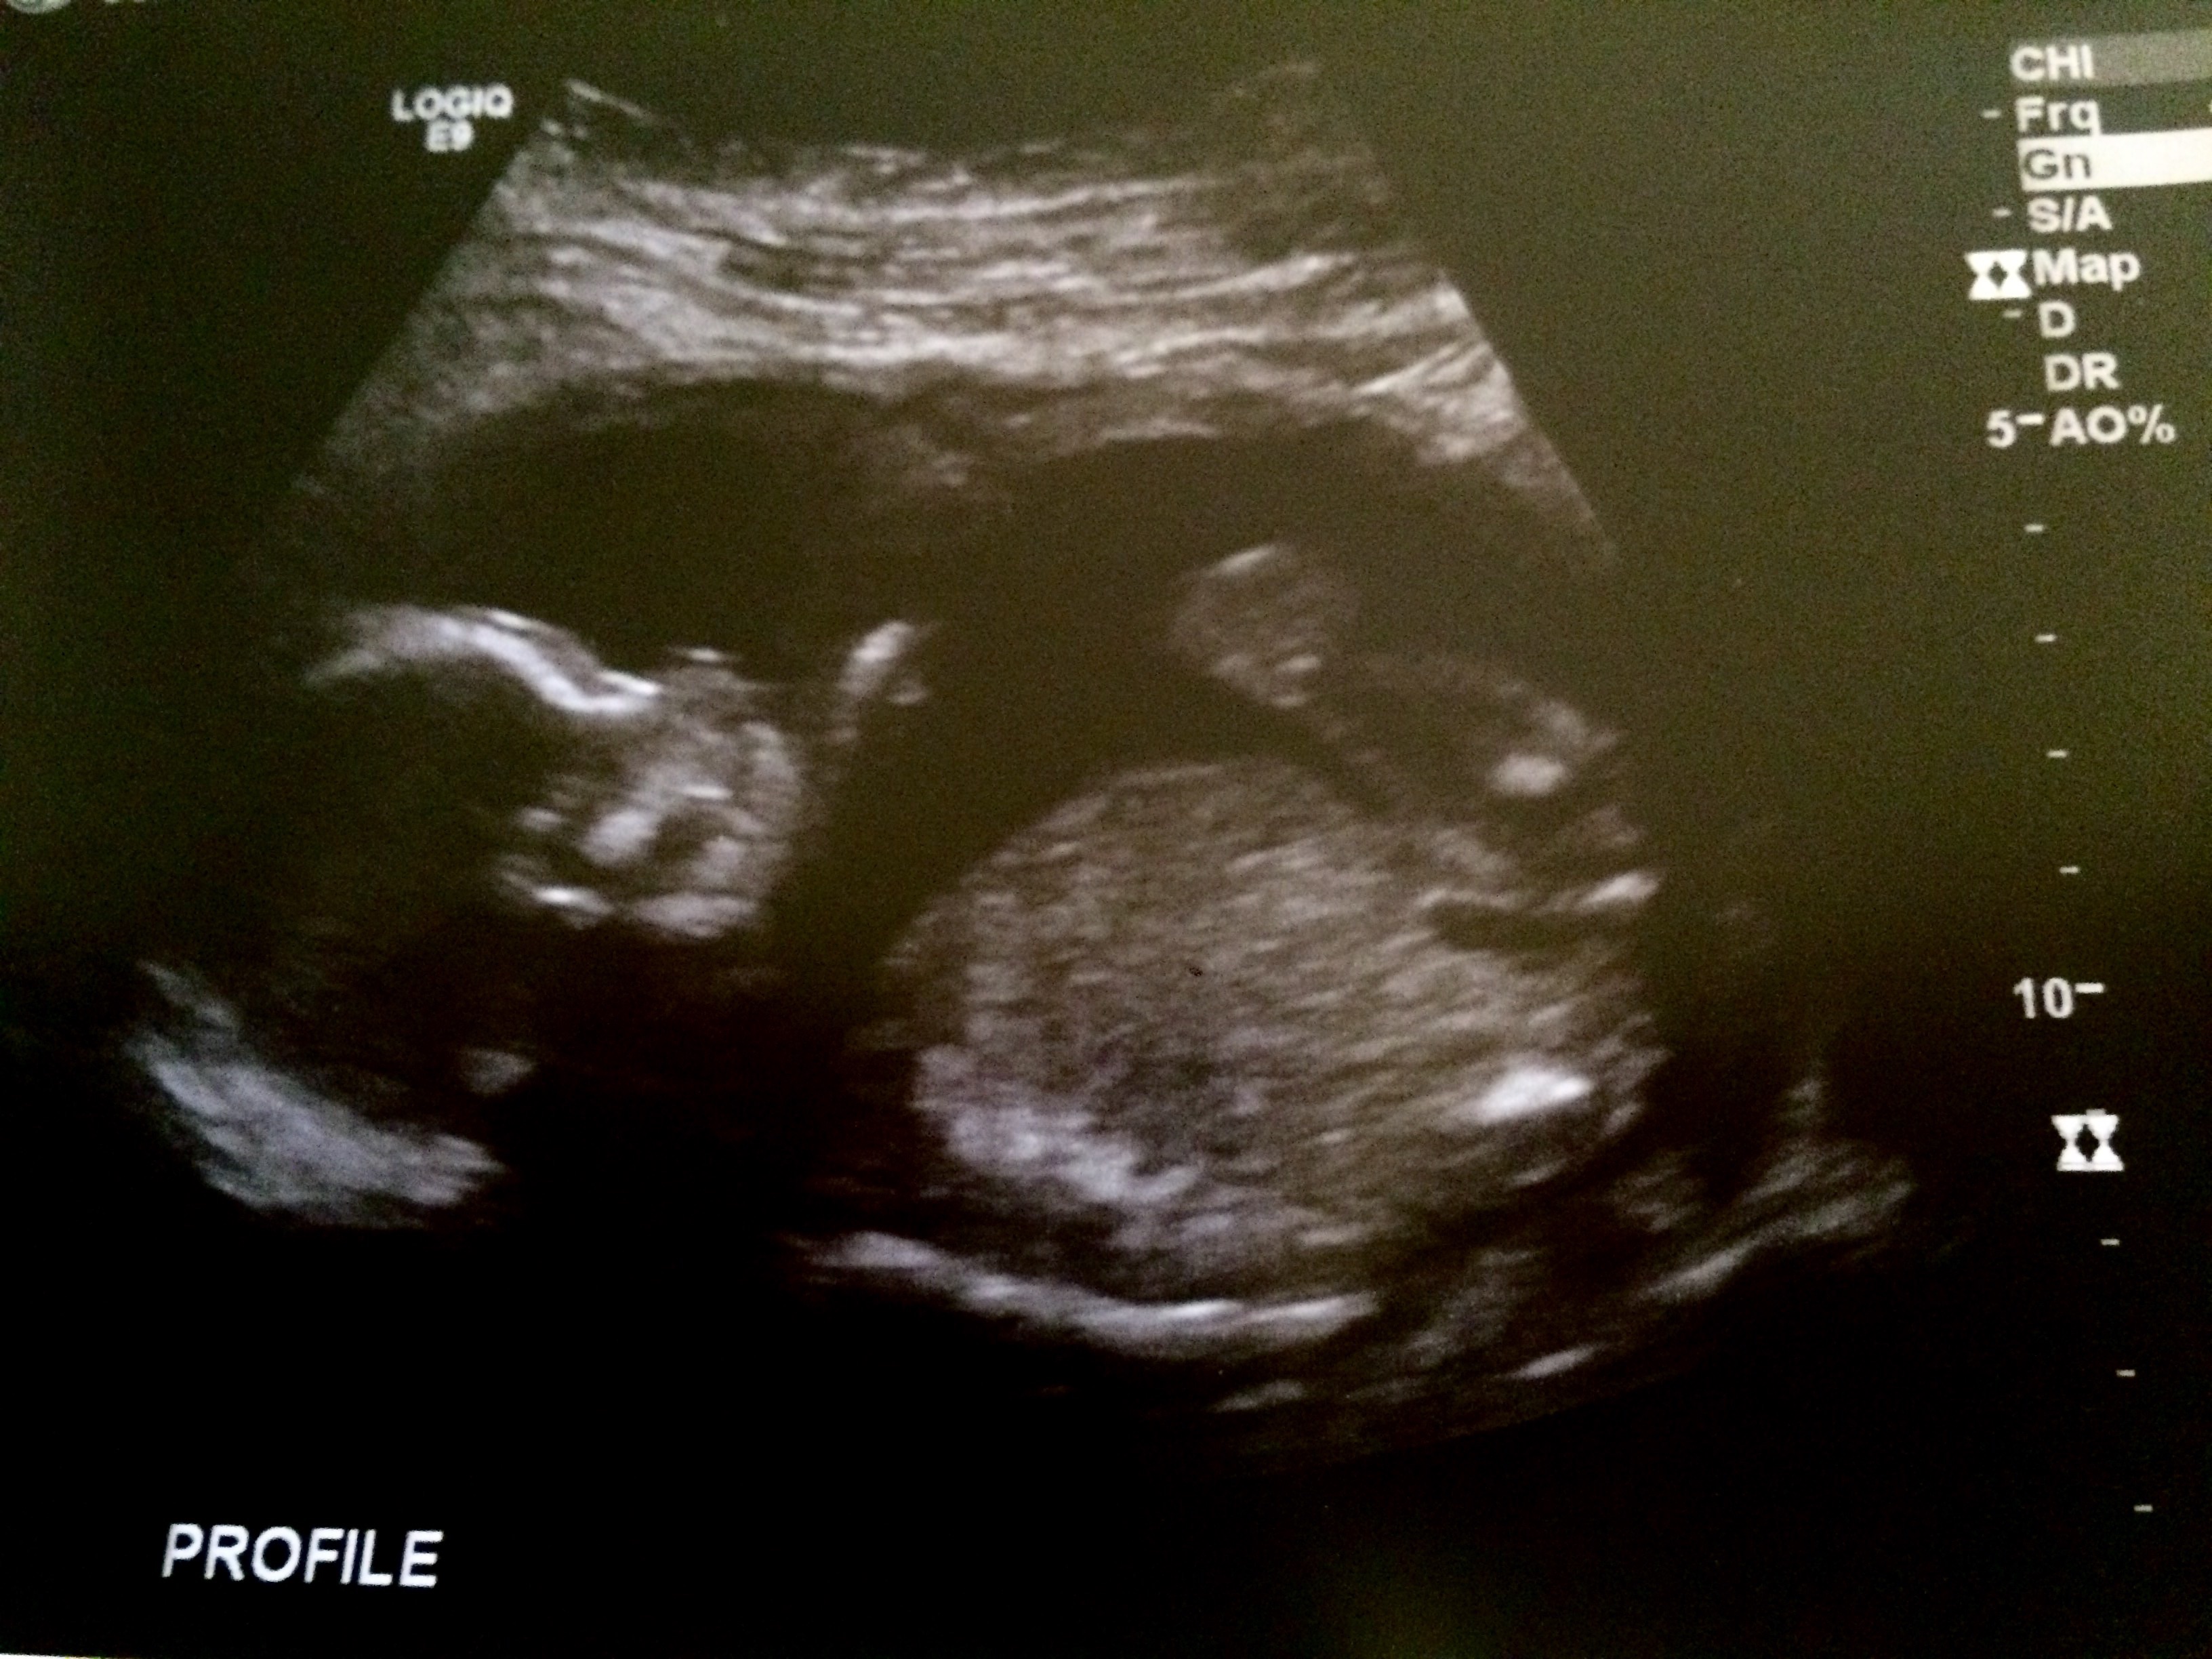

We had a scan on the 11th for a large cyst on my ovary was 13w 1d and husband asked about gender she said super early but could let us know what she thought it might be this is what she showed us.... husband is set that it is was it show but I feel it's super early and that's really really big since it shows half the size of its thigh (see profile pic it won't let me post)

Hello ladies I am 17+2 my first scan was Really clear we are not finding out the sex either so really excited. Please see attached photo feel free too guess